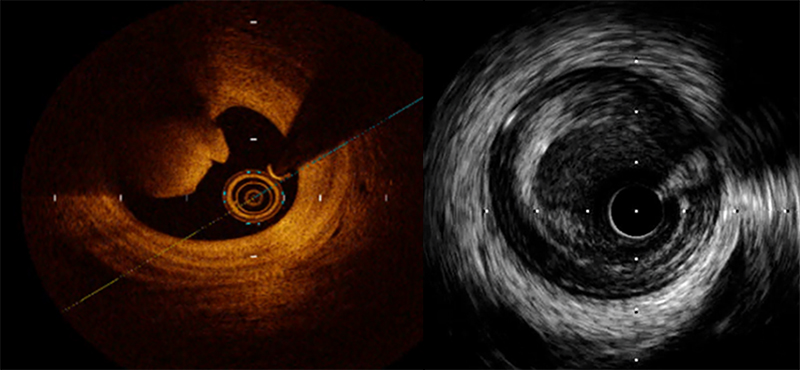

冠動脈内イメージングの技術進歩により、最近は動脈硬化の質を判定できるようになって来ました。特に光干渉断層法 (Optical Coherence Tomography: OCT)は近赤外線を用いた高解像度の画像構成技術で、最大の特徴はその高い解像度で血管内超音波検査(Intravascular Ultrasound:IVUS)の10倍の解像度を有しています。そのため,IVUSでは不可能であった血管の内膜・中膜・外膜の判別が可能で,プラークの性状や線維性被膜の厚さなども測定することができるようになりました。当院ではPCIのほとんどの症例に冠動脈内イメージング(IVUSまたはOCT)を使用して、プラークの性状判断をしています。プラークの性状が良くない患者さんには、冠動脈狭窄の進行予防目的として脂質を低下させる薬を積極的に使用して、PCIと薬物療法のハイブリッド治療を行っています。